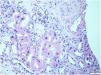

This biopsy, which included renal parenchyma consisting of cortex and medulla, with 32 glomeruli; 16 of them were sclerosed and the remaining showed slight segmental proliferation. The characteristic lesion is observed in the interstitium, at the level of the tubule cells, which show large, hyperchromatic and pleomorphic nuclei (Fig. 1). In the rest of the interstitium, histological lesions of acute tubular damage are observed (Fig. 2), associated with a patchy lymphoplasmacytic inflammatory infiltrate of moderate intensity, foci of fibrosis and tubular atrophy. The immunohistochemistry study showed negativity for LMP-1 (EBV), CMV, Herpes virus. Ki67 (cell proliferation index) is negative in atypical cells and less than 5% in tubular cells. The direct immunofluorescence study shows no significant deposits with the antisera studied. Electron microscopy showed a glomerulus with no significant lesions. Based on these data, the following diagnoses were made: Histological lesion pattern: (1) Global sclerosis in 50% of the glomeruli, with no defined lesion pattern in the non-sclerosed glomeruli. (2) Acute tubular damage at different stages with marked nuclear atypia in tubular epithelial cells. Note: The negativity of Ki67 in most of the atypical cells rules out the possibility of regenerative changes and suggests investigating the following entities as aetiological causes: heavy metal nephrotoxins, infection by viruses other than those already studied and karyomegalic interstitial nephritis.